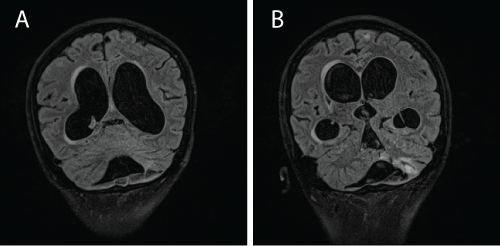

Despite receiving treatment, he became progressively disinhibited and drowsy. A repeated MRI revealed hydrocephalus (Figure 4a and 4b). A lumbar puncture showed a raised CSF protein > 6 g/dL with negative AFB smear and bactec culture for Mycobacterium tuberculosis was negative. A lumbar drained was inserted.

At this point, we entertained the possibility of MDR-TBM and CSF sample was sent for Xpert® MTB/RIF assay. This test was performed at a separate centre. Within a day, the result of Mycobacterium tuberculosis resistant to rifampicin was detected. The patient was labelled as MDR-TB and treatment regime was changed to pyrazinamide 1 gram daily, ethambutol 800 mg daily, amikacin 600 mg 5 times per week, moxifloxacin 400 mg od, ethionamide 500 mg morning and 250 mg in the evening, and clofaxamine 150 mg daily. The hydrocephalus was corrected with a ventricular-peritoneal shunt. A repeated MRI brain performed 3 months later showed resolution of the hydrocephalus (Figure 5a and 5b). He was planned for a total duration of second line anti-TB of 24 months. 2 months post treatment, CSF test for Xpert® MTB/RIF was negative and CSF culture sent earlier showed resistance to isoniazid, rifampicin and streptomycin. Hence, the exact diagnosis of MDR-TBM (a form of RR-TB). Currently he remains in remission of his SLE and has not shown any signs of relapse of TBM. His lungs are clear but he has grade 4/5 weakness of both left arms and legs. He has normal mental status.